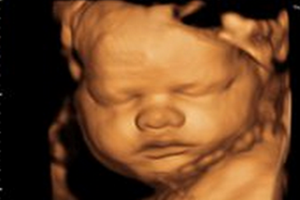

四维彩超提供了包括腹部、血管、小器官、产科、妇科、胎儿彩超图泌尿科、新生儿和儿科等多领域的多方面的应用。其结果是:能够显示您未出生的宝宝的实时动态活动图像,或者其它人体内脏器官的实时活动图像。

5、四维彩超检查也被称为“大排畸”检查。换言之,就是可以大范围的判断胎儿是否有缺陷。当然,由于胎儿发育过程还没有完,并且现有的机器设备不能非常清晰的看清楚胎儿所有的肢体器官,所以,超声诊断符合率不能达100%。

6、胎儿的某些部位不在超声检查范围内,例如,耳朵、性别、生殖器及颚弓。

7、四维彩超中胎儿四肢的检查,不包括指骨、趾骨的数目。